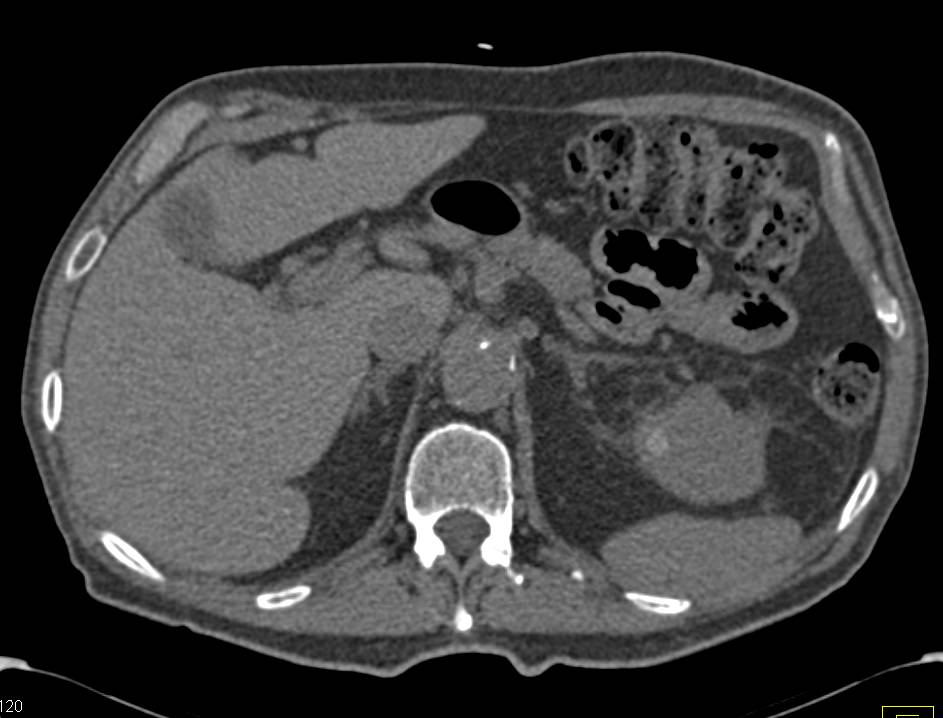

Numerous Cystic Renal Lesions Several of Concern for Malignancy